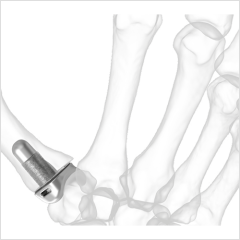

Explore our broad range ofOrthopedic Products

We are dedicated to improving the quality of life of patients suffering with bone and joint problems by delivering the latest medical devices that are proven to be effective and backed by scientific studies and research

• Surgical Devices